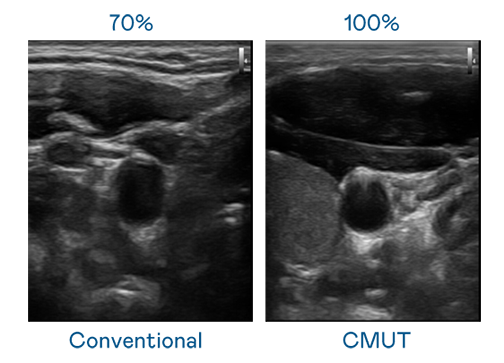

CMUT 技术是一种用电容式微机电元件来产生超音波讯号的技术。与传统 PZT 压电式技术相比,CMUT 频宽增加 30%,更宽频的超音波讯号让影像解析度大幅提升,是实现高影像品质医疗超音波扫描、促进精准医疗发展的关键技术。

超音波影像的解析度高低,首先取决于探头能发出的讯号频宽。GA黄金甲 CMUT 可提供高清晰的超音波讯号,提供高频宽、高灵敏度、影像纹理细节更高的超音波影像,协助医护人员缩短影像判读时间及利用精准的医疗影像进行诊断。